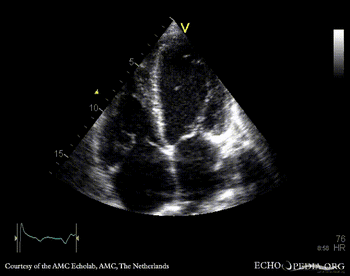

PLAX: thickend aortic valve and mitral valve PSAX: flattening of IAS, enlarged right ventricle